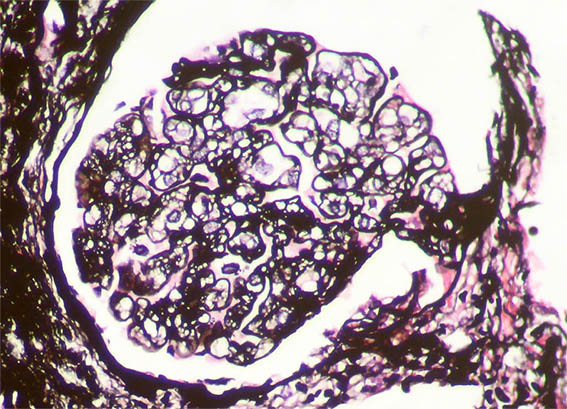

Se hace biopsia renal con impresión diagnóstica de lesión renal aguda. Ver las imágenes.

Figura 5. Plata-metenamina, X400.

Figura 6. Plata-metenamina, X400.

Figura 7. Plata-metenamina, X400. Mesangiolisis.